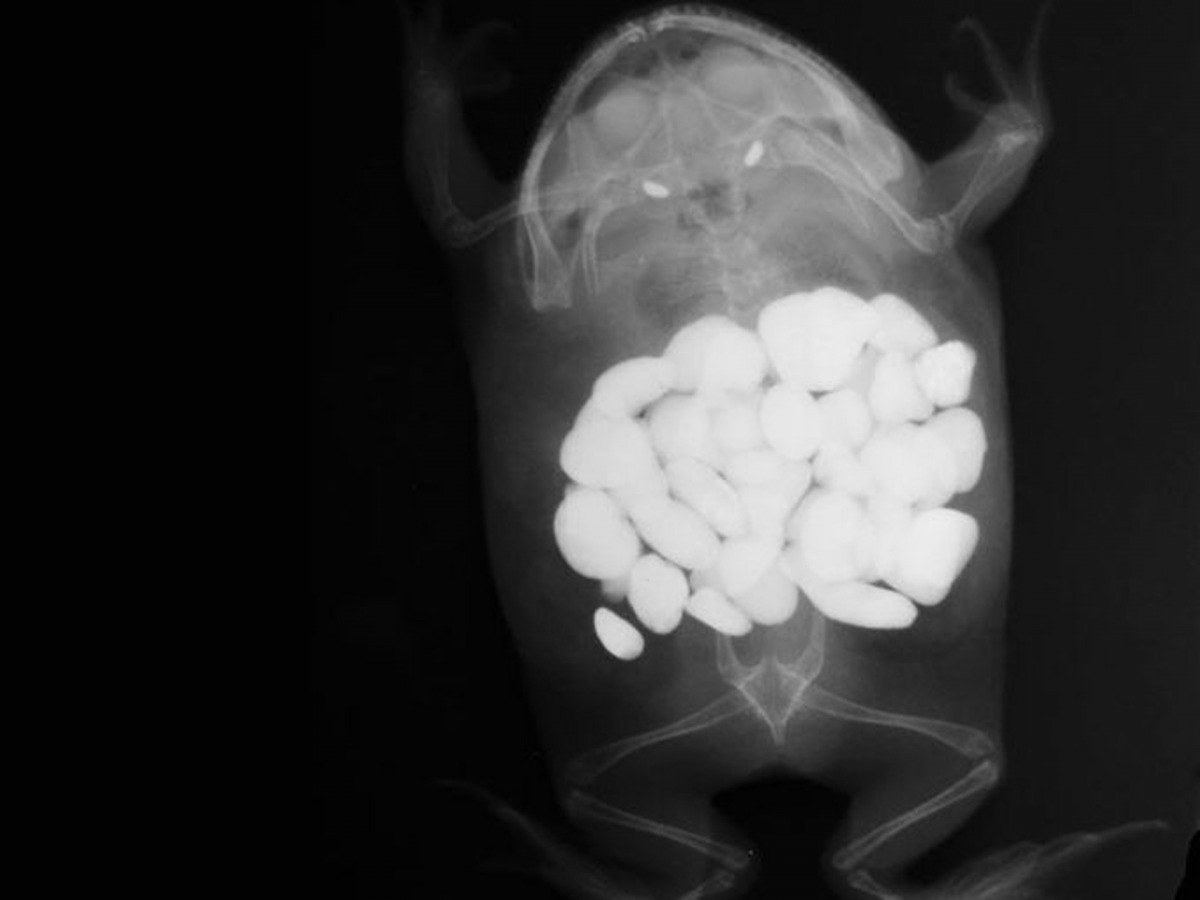

云云參賽作品中,來自德州「Paws & Claws」動物醫院的梅索尼耶(Shawn Messonnier)獸醫成為這次比賽冠軍,他表示早前曾為一隻青蛙照X光時,發現牠胃中出現多達30粒顆石頭,主人後來才驚覺寵物青蛙竟把籠內用作裝飾的石頭全部吞下,Shawn更笑說青蛙施手術後經已完全康復,主人從此亦不敢再於籠內放置任何石頭。